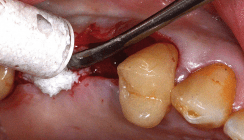

Die Zähne 26 und 27 wurden extra­hiert. Der Bone Splitting in Regio 24 wurde mithilfe einer minimalinvasiven Schnittführung durchgeführt (Abb. 5). Hierzu bieten sich geeignete diamantierte Scheiben oder Piezosurgery-Ins­trumente an. Um die Lateralisierung der Knochenlamelle besser steuern zu können sowie eine unkontrollierte Fraktur zu vermeiden, wurden neben der krestalen Inzision zusätzlich zwei vertikale Frakturlinien gesetzt. Es wurden drei Implantate in Regio 24 sowie in möglichst bukkaler Position der Ex­traktionsalveolen 26 und 27 gesetzt. Ein Zugang zum Sinus mithilfe der Präparation eines Knochenfensters in Regio 26 wurde geschaffen (Abb. 6).

Sämtliche periimplantäre Knochen­defekte sowie der Sinus in Regio 24 bis 27 wurden mit dem Knochenaufbaumaterial augmentiert, das zuvor in physiologischer Kochsalzlösung hydratisiert wurde. Es wurde darauf geachtet, durch eine zusätzliche laterale Augmentation, v. a. in der Bone Split-Region 24, eine ausreichende Rekonturierung des teilweise stark atrophierten Kieferkamms zu erzielen (Abb. 7). Das Knochenersatzmaterial wurde mit zwei Membranen (OSSIX PLUS je 25 x 30 mm, ­REGEDENT) abgedeckt (Abb. 8). Zur besseren Stabi­lisierung der augmentierten Region wurde die Membran mit einer Intra­periostalnaht fixiert. Aufgrund der guten Anliegeeigenschaften kann auf eine zusätzliche Fixierung verzichtet werden. Der spannungsfreie Wundverschluss wurde durch Matratzennähte erreicht (Abb. 9).